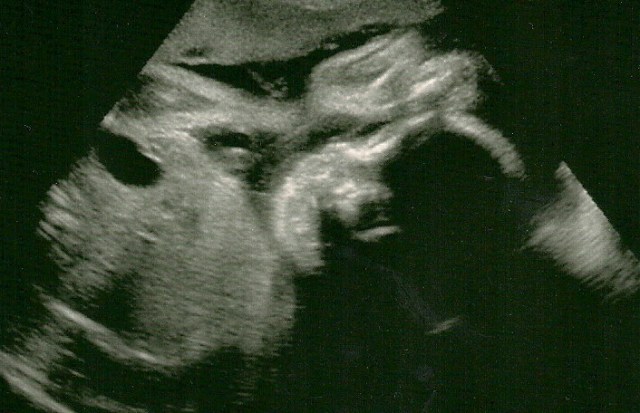

At the hospital this morning I snuggled up in a comfy bed while the delightful nurse strapped a couple monitors on my gorgeous round belly. Listening to the heart beat and studying the printout from the machine (reminiscent of an EKG), she comments on what a “beautiful baby” it is right away. As the test continues she proceeds to gush about what a healthy baby it seems to be. At first I took this with a grain of salt, but she kept at it. The “most beautiful strip I’ve seen in a long time,” she finally says. This means healthy baseline heart rate, with nice variability, accelerations with activity, and no decelerations. It was cool to experience; I would feel baby would do one of it’s fabulous contortions, and I could hear the heart rate increase. Incidentally, she also suggested that it could be a boy. Not only because I’m carrying “small” as I did with my last Boy, but because a baseline heartrate of about 120 like this is often a boy, whereas girl’s are often around 140. Hmmm. She showed the strip to the doctor, who concurred it is a beautiful, strong, healthy baby. A bit kerflumpt, I thanked her for such a delightful start to my day, and then SHE said it was a treat for HER to see SUCH a great test!